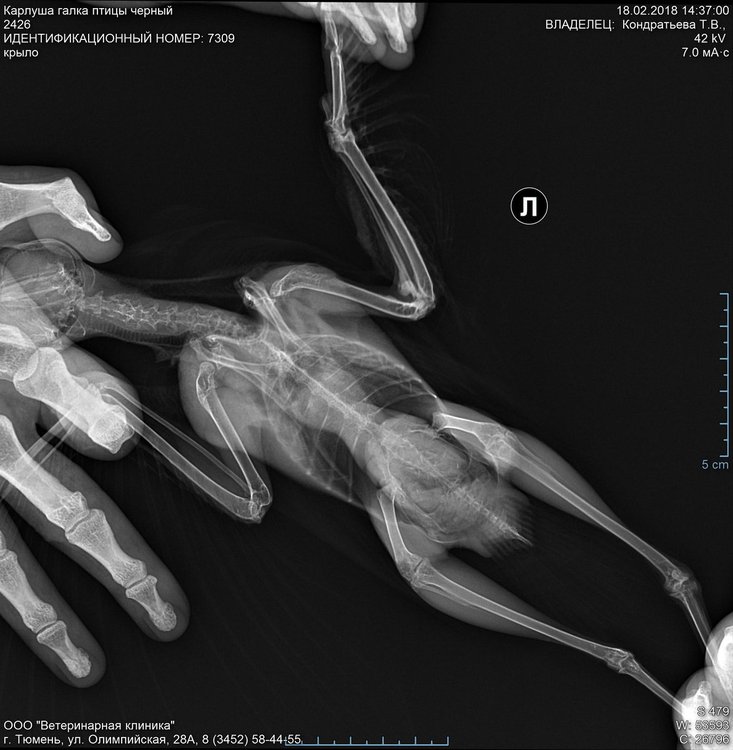

Доброго времени суток! Прошу совет по здоровью, рентгеновские снимки прилагаю.

11 декабря 2017 г. птица подобрана с улицы со сломанным крылом. Перелом закрытый. Открытых ран и других повреждений не обнаружено. Оперение на вид чистое от паразитов.

Карлуша_галка_2018-02-18_1_крыло.jpg

Карлуша_галка_2018-02-18_2_крыло.jpg